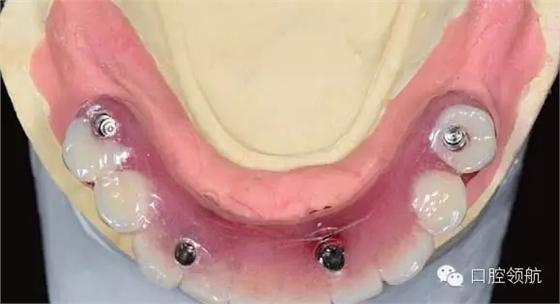

下頜為十?dāng)?shù)年前制作的三組金屬烤瓷橋修復(fù)體。右下4、5、7帶缺失的6;右下3、1及左下1、2帶缺失的右下2;左下3、4、5、8帶缺失的6、7,左下8修復(fù)后牙齒自然脫落,全景片無左下8的影像。幾乎所有的余留牙周圍的骨質(zhì)均吸收到根尖1/3。臨床上三組下頜金屬烤瓷橋均有較大幅度的松動(圖6-7,圖6-8)。

圖6-7 術(shù)前口內(nèi)照片

患者為64歲女性,自述下頜咬合無力,牙齦經(jīng)常出血,有反復(fù)腫脹史,要求拔除后種植修復(fù)。